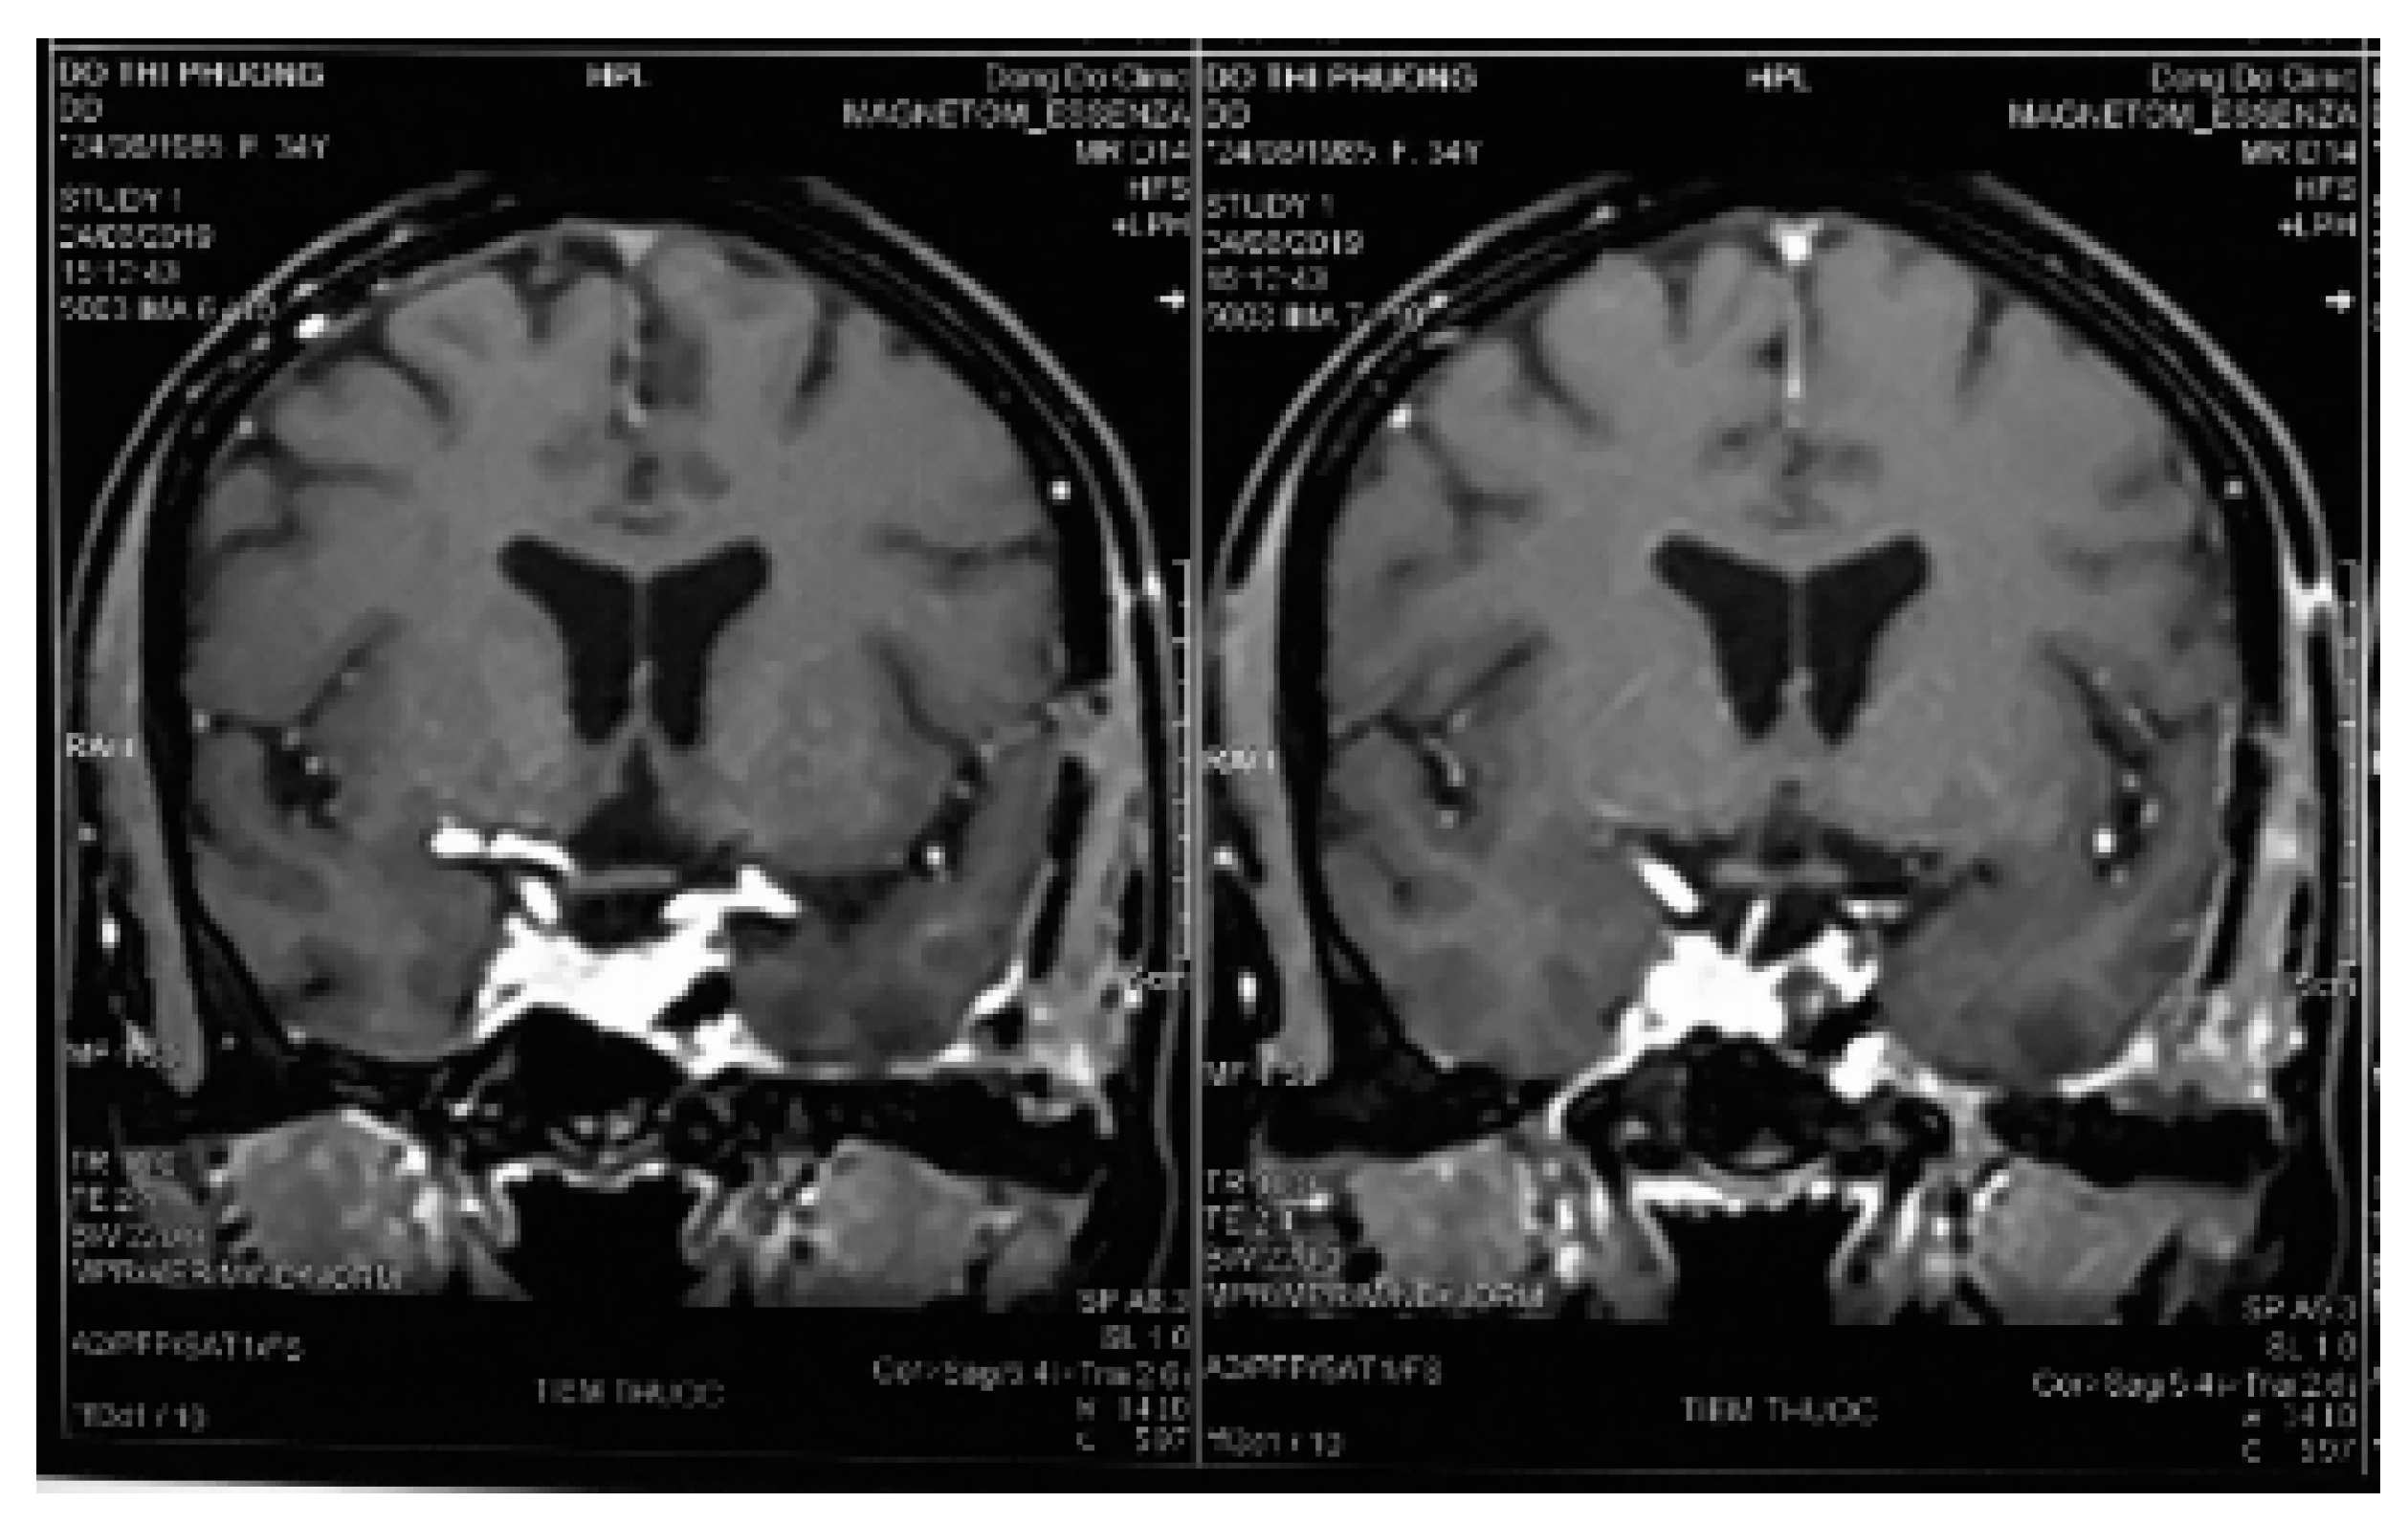

Histopathological examination of the mass revealed a cavernous haemangioma with many large cystically vessels filled by blood cells with an irregular thickness of the walls covered by benign flat endothelial cells (Figure 2). After surgery, the patient presented left ptosis, left eye exotropia (due to trauma of the third nerve), and left maxillary numbness (due to trauma of the V2 nerve) (Figure 3). However, the symptoms of third nerve palsy completely recovered after rehabilitation for 3 months. At the moment, the patient only has permanant numbness in the left cheek.

Figure 2.

Histopathology revealing large numbers of thin-walled vascular sinusoids, with a single layer of endothelium-lined capillaries, and scanty connective tissue. (a) H&E, 100×; (b) H&E, 250×. H&E, hematoxylin and eosin.